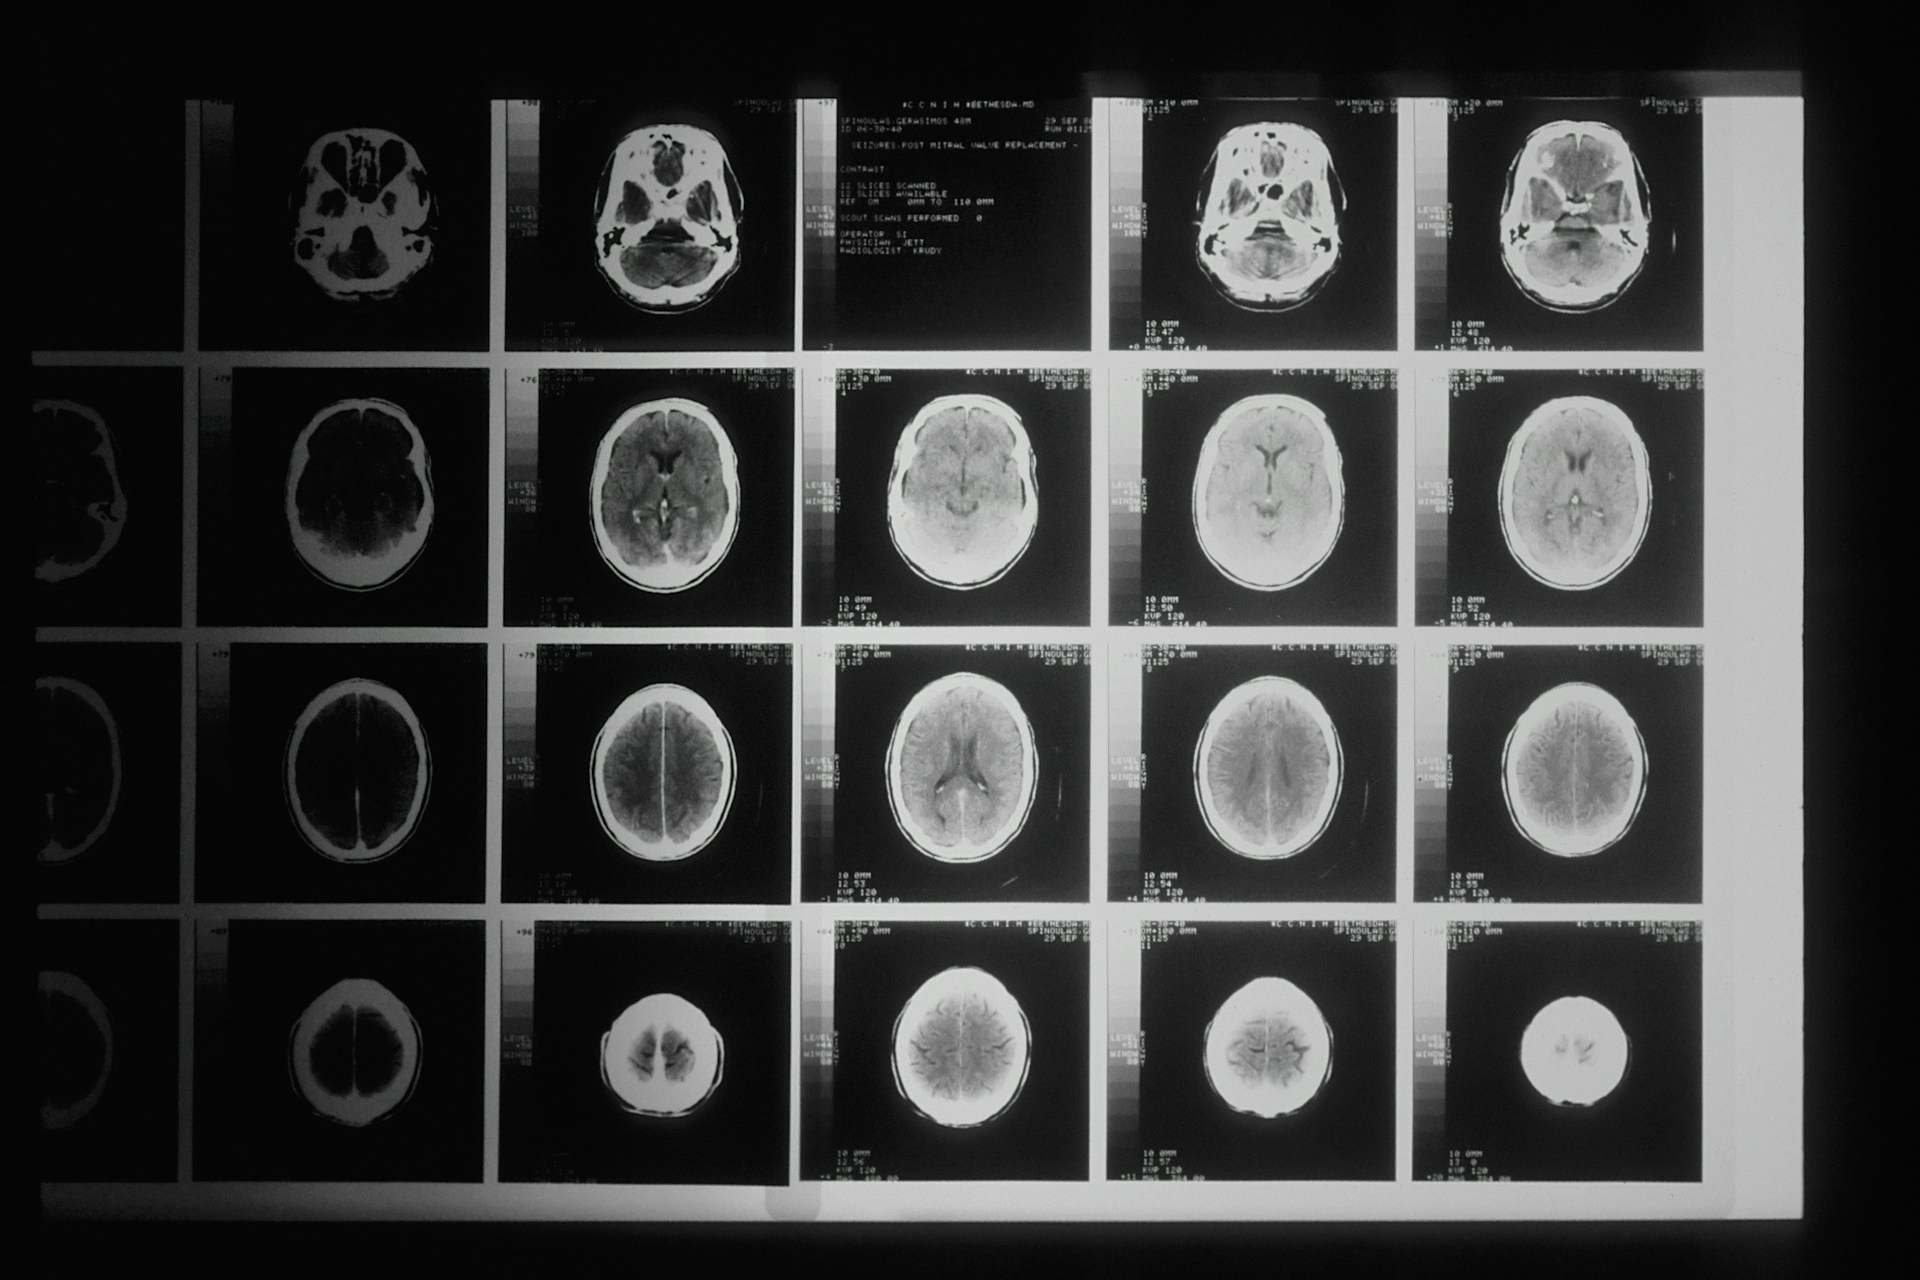

Untuk mendiagnosis tumor, dokter biasanya akan melakukan serangkaian pemeriksaan. Pertama, dokter akan melakukan pemeriksaan fisik untuk mendeteksi adanya benjolan atau perubahan yang mencurigakan. Selanjutnya, bisa dilakukan tes pencitraan seperti USG, CT scan, atau MRI untuk melihat lebih jelas ukuran dan lokasi tumor. Jika diperlukan, dokter juga akan melakukan biopsi, yaitu mengambil sampel jaringan tumor untuk diperiksa lebih lanjut di laboratorium.